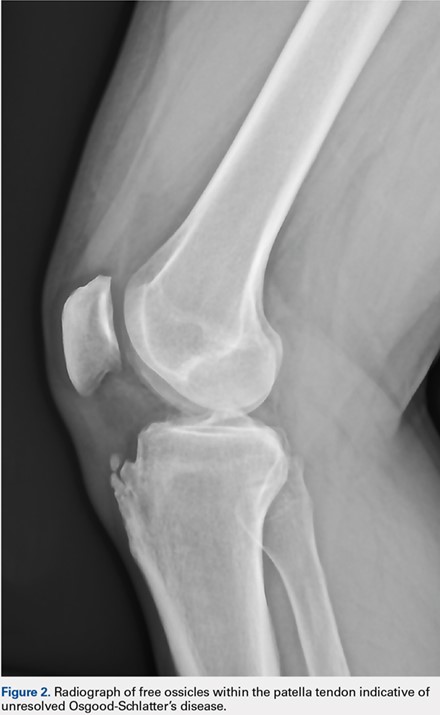

Of the 197 patients, only 1 was found to have a multipartite patella (prevalence, 0.5%). This 37-year-old male patient showed a right bipartite patella located in the superior-lateral aspect (Figure 1).